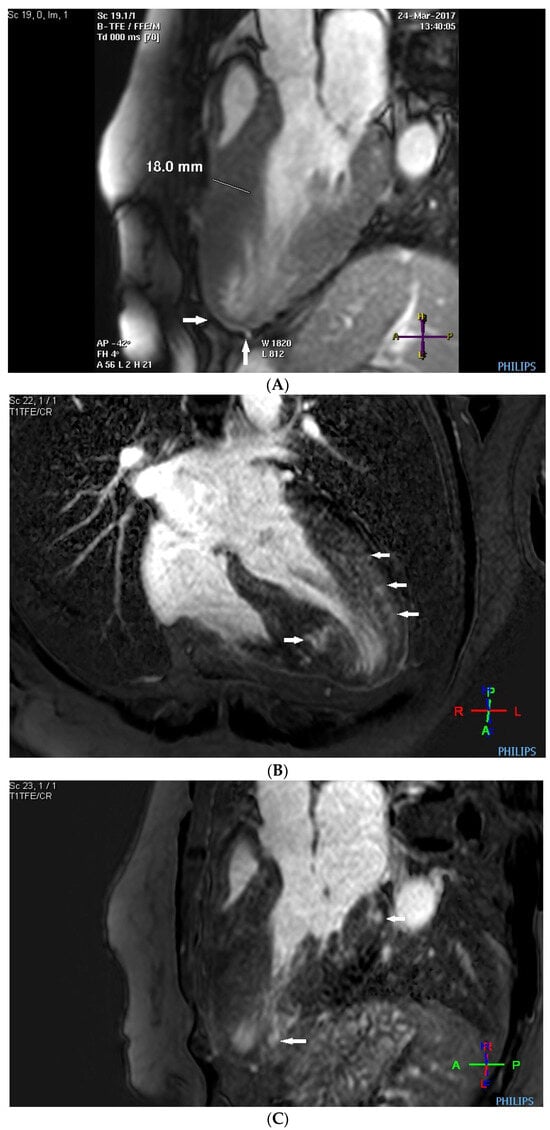

2. Case Description